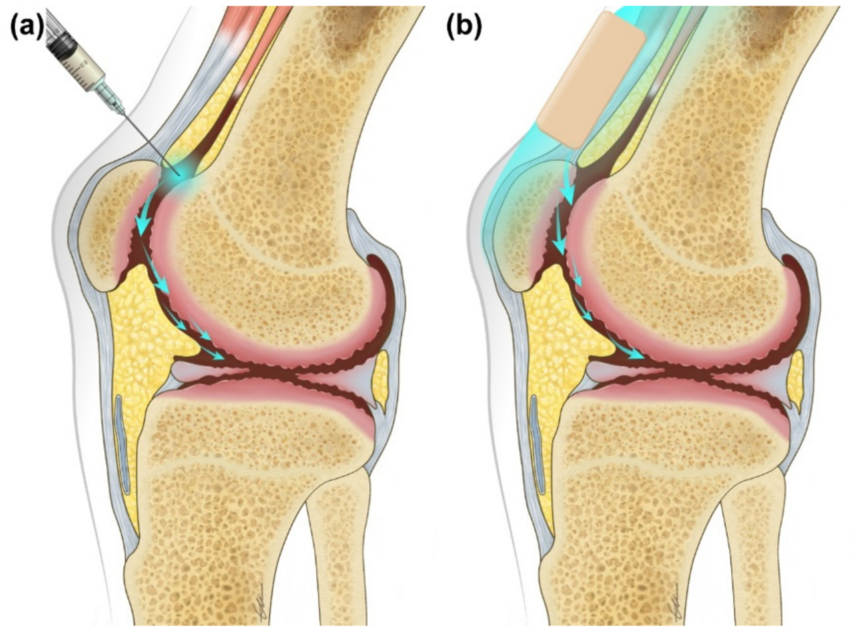

Intra-Articular Injections

In both arthritis and osteoarthritis, fluid may accumulate in the joint. Aspiration of this fluid for microscopic analysis can often help determine the underlying cause of the arthritis. Following fluid removal, a corticosteroid injection may be administered directly into the joint to relieve symptoms quickly and reduce inflammation.

In our clinic, both intra-articular injections of sodium hyaluronate and PRP treatments are offered. Please contact our clinic to learn about the indications for these therapies.